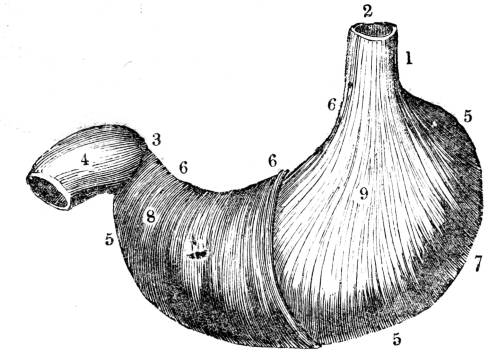

Fig. CXXXV.—

View of the Air Tubes and Lung.

1. The larynx. 2. Trachea. 3. Right bronchus. 4.

Left bronchus. 5. Left lung; the fissures denoted by the

two lines which meet at 6, dividing it into three lobes,

and the smaller lines on its surface marking the division of

the lobes into lobules. 7. Large bronchial tubes. 8. Minute

bronchial tubes terminating in the air cells or vesicles.

1. The trachea. 2. The right and left bronchus; the left

bronchus showing its division into smaller and smaller

branches in the lung, and the ultimate termination of the

branches in the air vesicles. 3. Right auricle of the heart.

4. Left auricle. 5. Right ventricle. 6. The aorta arising from

the left ventricle, the left ventricle being in this diagram

concealed by the right. 7. Pulmonary artery arising from

the right ventricle and dividing into, 8. The right, and

9. The left branch. The latter is seen dividing into smaller

and smaller branches, and ultimately terminating on the

air vesicles. 10. Branches of one of the pulmonary veins

proceeding from the terminations of the pulmonary artery

on the air vesicles, where together they form the net-work

of vessels termed the Rete Mirabile. 11. Trunk of the

vein on its way to the left auricle of the heart. 12.

Superior vena cava. 13. Inferior vena cava. 14. Air vesicles

magnified. 15. Blood-vessels distributed upon them.